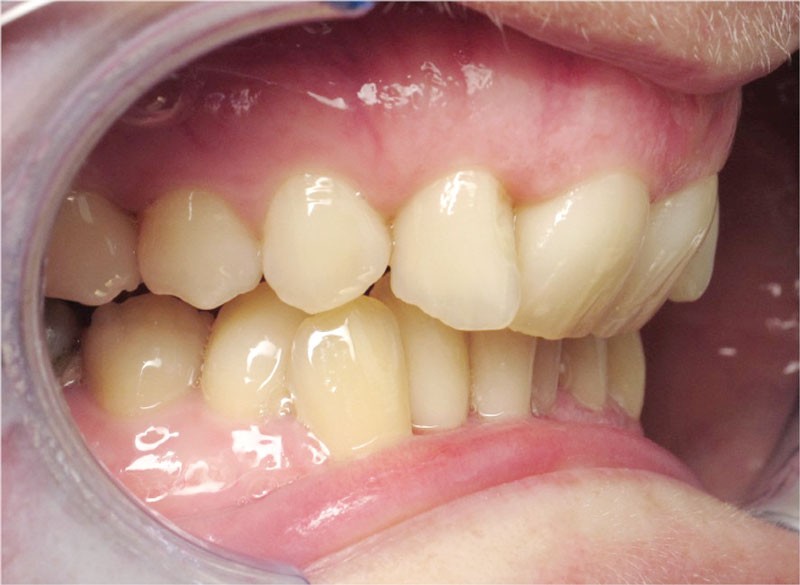

Un appareillage Damon métal a été mis en place, réalisé à partir d’un set up numérique Insignia pour obtenir un contrôle précis des torques et de la forme d’arcade et réduire le temps de finition grâce à un collage indirect très précis.

De larges surélévations postérieures étalées ont été mises en place et la patiente a porté des élastiques précoces suivant les principes de la technique Damon. Les 14 et 24 rempliront le rôle des 13 et 23.

L’objectif, en utilisant la technique Insignia est de réduire le temps de traitement de 28 à 18 mois avec 12 rendez-vous (fig. 5 à 14).